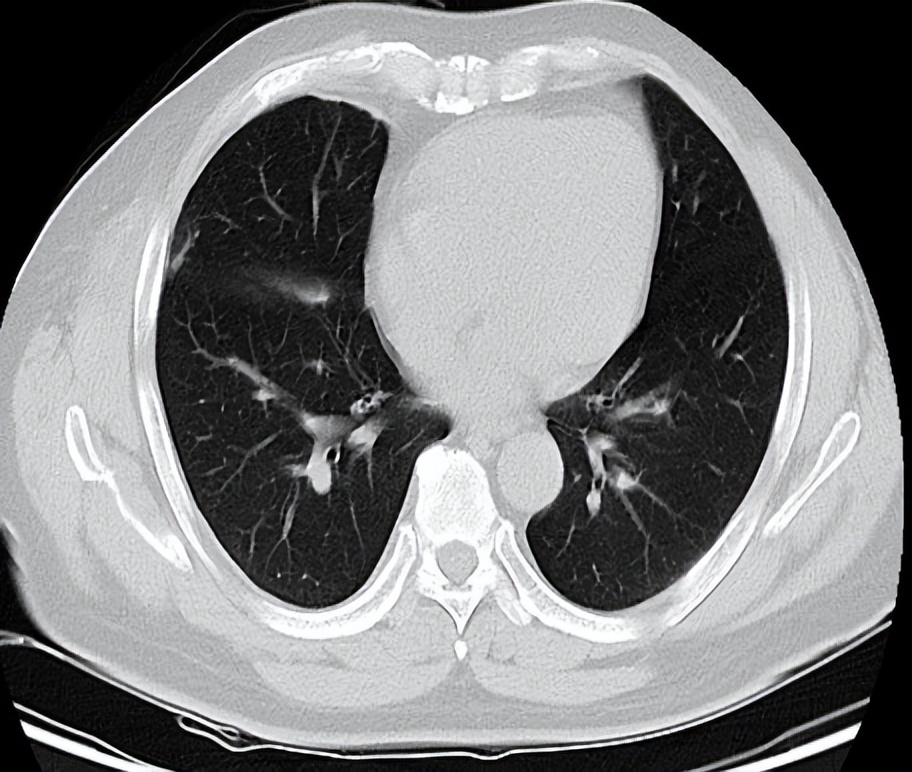

患者男性,56岁,因反复咳嗽入院 2016.12.22行胸部CT检查提示:右侧胸膜为广泛增厚呈不规则状、结节样的增厚,右侧胸腔可见有大量的胸腔积液。纵隔、肺门淋巴结不大,考虑胸膜间皮瘤可能。于2017-1-10行VATS右胸膜活检术,术后病理提示(右胸膜)恶性肿瘤,结合酶标结果考虑恶性间皮瘤。免疫组化结果:TTF-1(-),NapsinA(-),CK7(+),WT-1(+),CK5/6(+),CAL(+),MC(+),D2-40(+)。术后恢复良好,术后予抗炎、补液等对症治疗,诊断为:右侧胸膜间皮瘤cT4N1M0-IIIB期。患者于2017-2至2017-5行AP(培美曲赛联合顺铂)方案化疗共4周期。2017-6-27胸部CT检查提示疗效部分缩小(PR)。